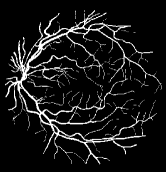

As pointed out in recent works [15, 17], a good semantic segmentation network should learn multi-level features. Further, it should have multiple stages with different receptive fields to learn more inherent features from different scales. FCN, taken as an example, uses skip connections to fuse multiple stages outputs, as well as the HED network, in which a series of side-output layers are added after each stage in VGGNet. The HED network was first proposed for edge detection, and further used for image-level vessel segmentation in recent studies [6, 16], with significant performance. However, our experimental results show that such network architecture is not appropriate for vessel segmentation directly. Figure 1 provides such an illustration. Reasons for this phenomenon are straightforward. On one hand, the side-output of the first layer often contains too many noises. On the other hand, the features produced by the last side-output layer are too coarse due to information loss of pooling operation. Obviously, the inaccurate vessel map of side-output1 and side-output4 should have negative impacts on the final segmentation result.

With the deepening of DSN network, the receptive field of each side-output layer gets larger, which makes the corresponding vessel map much blurrier as observed from the first row in Figure 1, especially for side-output4. These observations inspired us to pass low level fine semantic information to high levels to alleviate the blurring situation.

Bottom-top short connections aim to refine high-level segmentation results. However, we can observe from the first two rows in Figure 1 that the vessel map generated by the first side-output layer contains too many noises while the map generated by the last side-output could capture the main vessel structure. Therefore, we propose delivering high-level structural information to the first side-output layer to reduce its noises. We implemented this kind of information delivery by a top-bottom short connection from conv4 to feat_conv1, which can been seen in Figure 4. We first convolved the last convolution of conv4 using 1 convolution kernels with size 33. Then the obtained feature map are up-sampled 8 to get feat_4_1. The information (feat_4_1) passed from conv4 are concatenated with feat_conv1 to form feat_conv1_fuse (see Figure 5). At last, one hand hand, we perform a 11 convolution operation on feat_conv1_fuse to get the information (feat_1_2) delivered to feat_conv2. On the other hand, we performed convolution operation with a kernel size of 11 and sigmoid transformation for feat_conv1_fuse sequentially to obtain the segmentation result (side 1). At last, side 1 is compared with the ground truth to get the loss of the first side-output layer.

In addition, we can observe from Figure 1 that the side-output1 and side-output4 of the BTS-DSN were more accurate compared with those of the DSN.

The segmentation results of image-level input BTS-DSN on three datasets are shown in Figure 6. We can observe from Figure 6 that the binary vessel segmentation results of BTS-DSN can recognize very coarse vessels. However, for thin vessels, the segmentation results are intermittent and many thin vessels cannot be identified.